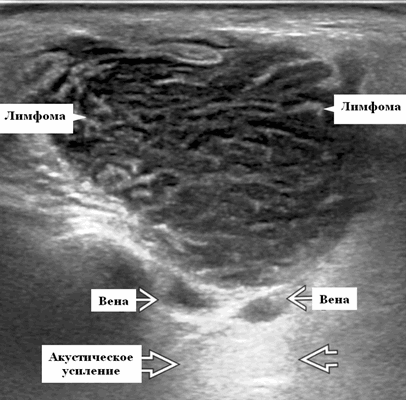

Околоушная неходжкинская лимфома на УЗИ

Ключевые факты при ультразвуковой диагностике слюнных желез

- Узловая неходжкинская лимфома (НХЛ): одиночные или множественные увеличенные яйцевидные внутрипаротидные лимфатические узлы, которые на УЗИ гомогенно гипоэхогенны по отношению к паренхиме околоушной железы, эхо-картина сетчатая. Заднее акустическое усиление. Выраженная внутриузловая гиперваскуляризация

Лучший диагностический признак на УЗИ при узловой НХЛ: множественные однородные, четко выраженные образования околоушных желез и лимфаденопатия верхних отделов шеи. Паренхиматозная НХЛ: инфильтративная околоушная опухоль, фон СШ, BLEL

Размер. Узловая НХЛ. Обычно 1-3 см. Паренхиматозная НХЛ может поражать большую часть околоушной и / или поднижнечелюстной железы

Морфология. Узловая НХЛ. Обычно хорошо очерченное образование от округлой до яйцевидной формы, иногда дольчатой или неправильной формы. Иногда может быть матовой, но редко некротической. Паренхиматозная НХЛ имеет распространенную инфильтрацию или нечеткое образование. Может быть солидной или (реже) кистозной

Серошкальное УЗИ. Узловая НХЛ. Одиночные или множественные увеличенные яйцевидные внутрипаротидные лимфатические узлы. Гомогенно гипоэхогенный по отношению к паренхиме околоушной железы. Сетчатый эхосигнал. Заднее акустическое усиление. Первичная паренхиматозная НХЛ. Рассеянный, неоднородный эхосигнал; нечеткие, гипоэхогенные, похожие на опухоль участки. В пунктате внутрикистозная или паренхиматозная кальцификация из-за конечной стадии воспалительного изменения. Небольшие кистозные области образуются из-за сдавления терминальных протоков лимфоидной гипертрофией. Множественные небольшие гипоэхогенные участки (представляют собой лимфоидные агрегаты), разбросанные на фоне ткани слюнной железы. Изменения могут имитировать хронический сиалоаденит и диагноз часто ставится при биопсии. На УЗИ необходимо искать аналогичное поражение других слюнных и слезных желез, фон синдром Шегрена, BLEL. Может иметь или не иметь перипаротидную и шейную лимфаденопатию